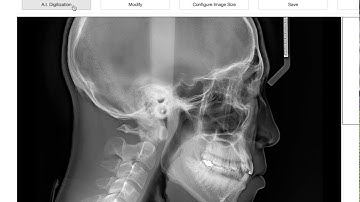

CephNinja custom analysis creation demo for orthodontists. AI-Powered Cephalometric Analysis